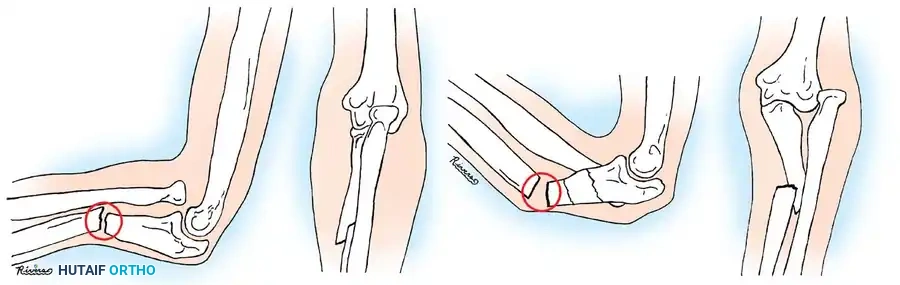

BIOMECHANICS AND PRINCIPLES OF CLOSED REDUCTION

The forearm functions as a complex, articulated ring. The radius and ulna are bound by the interosseous membrane, and their relationship dictates the critical motion of pronation and supination. When a fracture occurs, the muscular attachments exert predictable deforming forces on the fracture fragments.

For successful closed reduction, the distal fragment must be aligned with the proximal fragment, which is controlled by these muscular forces. Most authors agree on the following immobilization positions based on the level of the fracture:

* Distal Third Fractures: The arm should be placed in pronation to counteract the pull of the brachioradialis and pronator quadratus.

* Middle Third (Diaphyseal) Fractures: The arm should be placed in a neutral position.

* Proximal Third Fractures: The arm should be placed in supination to match the proximal fragment, which is strongly supinated by the unopposed action of the biceps brachii and the supinator muscle.

Clinical Pearl: King’s Principle dictates that the radial bicipital tuberosity proximally and the radial styloid distally are best visualized in maximal supination. It is highly recommended that these two anatomical landmarks be properly aligned on the anteroposterior (AP) radiograph to ensure rotational reduction is accurate.